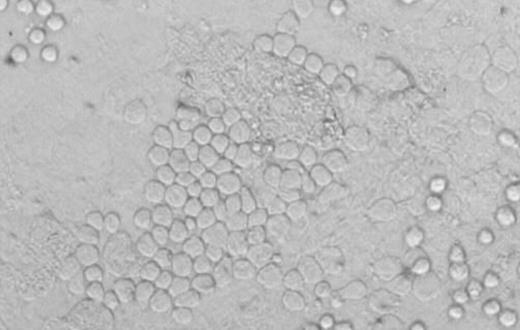

INTRODUCTION: Delayed engraftment remains a serious problem following cord blood (CB) transplantation. It may be due, at least in part, to the limited dose of CB hematopoietic stem and progenitor cells (HSPC) transplanted. Limitations associated with HSPC dose may be reduced by the transplantation of 2 CB units. In an accompanying abstract, de Lima et al. report in detail on an ongoing MDACC randomized study in which patients received double CB units as either 2 unmanipulated units (2×UN), or 1 unmanipulated and 1 ex vivo expanded CB unit (UN+EX). This study has revealed that one CB unit ultimately predominates as the source of long-term, sustained hematopoiesis. We hypothesized that the number of primitive HSPC in the CB unit might ultimately predict which CB unit would ultimately prevail. The in vitro cobblestone area-forming cell (CAFC) assay was used to provide a measure of primitive components of the CB HSPC in each unit. A photomicrograph of a typical cobblestone area (CA) derived from a single CB-derived CAFC is shown. (Figure) CA persisting in in vitro culture for ≥6 weeks (derived from CAFCwk6) represent relatively primitive HSPC and their numbers may provide a qualitative profile for CB units. We hypothesized that of the two CB units transplanted, the one with the greater number of CAFCwk6 would ultimately persist long-term in the patient.